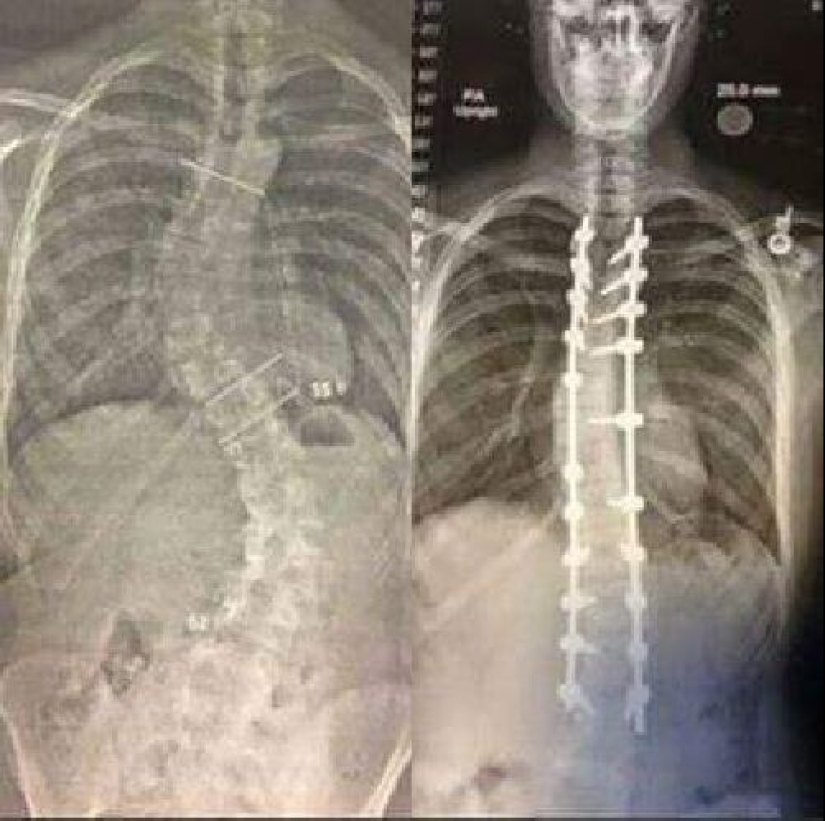

Radiografía de la espalda antes y después de la cirugía de alineación espinal debido a escoliosis